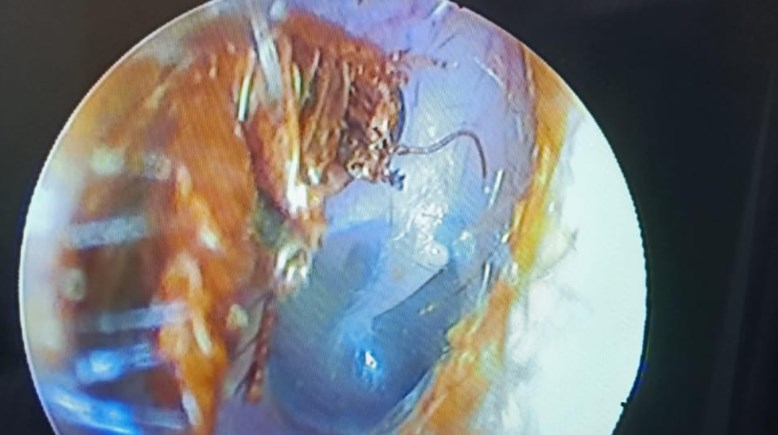

حماية الأذن من الحشرات

واقعة غريبة.. حكاية شاب أنقذه طبيب من صرصور علق بأذنه